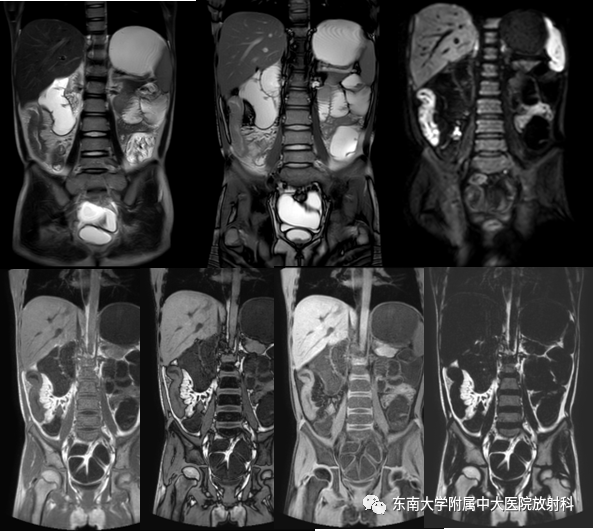

克罗恩病

病例

•男,14岁

•主诉:因“间断腹痛1年,加重伴大便次数增多1月”入院

•患者1年前无明显诱因下出现腹痛,主要位于脐周,呈阵发性发作,未予重视。1年来症状时有发作,约1-2次/周,未正规就诊治疗。1月前患者自觉腹痛加重,伴有大便次数增多,约3次/日,稀糊状。外院胸腹部CT:1、胸部平扫未见异常;2、升结肠及部分横结肠管壁增厚,考虑克罗恩病可能,建议肠镜检查。彩超:肝胆胰脾未见异常。予以“甲泼尼龙、奥硝唑、头孢”等治疗5天,后腹痛症状有所缓解